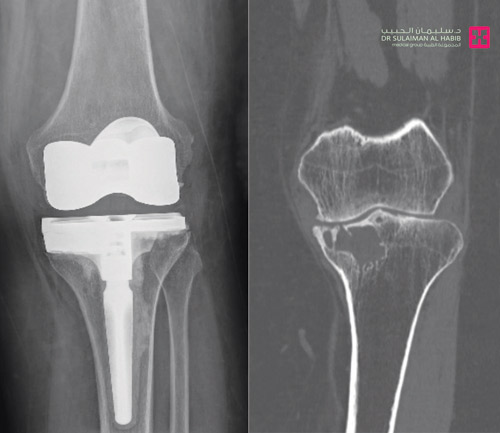

مستشفى الدكتور سليمان الحبيب بالفيحاء في جدة يستأصل ورماً ويستبدل مفصل الركبة

أجرى مستشفى الدكتور سليمان الحبيب بالفيحاء في جدة عملية معقدة لاستئصال ورم دموي واستبدال مفصل الركبة لسيدة تبلغ من العمر 48 عاماً، كانت تشتكي من صعوبة المشي والحركة مع ألم شديد في الركبة يمنعها من المشي وممارسة نشاطها اليومي. ذكر ذلك د. أنس نوح، استشاري طب وجراحة العظام والمفاصل، رئيس